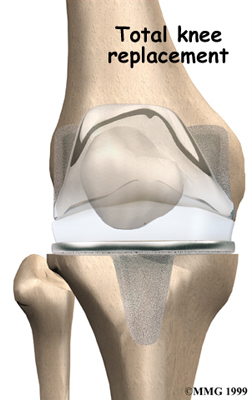

Artificial Knee Replacement

An artificial knee replacement is the ultimate solution for advanced knee OA.

Surgeons prefer not to put a new knee joint in patients younger than 60. This is because younger patients are generally more active and might put too much stress on the joint, causing it to loosen or even crack. A revision surgery to replace a damaged prosthesis is harder to do, has more possible complications, and is usually less successful than a first-time joint replacement surgery.

Related Document: FYZICAL Falls Church's Guide to Artificial Joint Replacement of the Knee